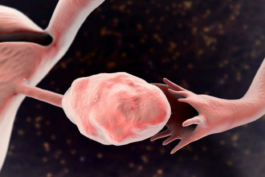

Los ovarios son dos glándulas reproductoras situados a ambos lados del útero, en la pelvis, y no están unidos directamente con los órganos del aparato reproductivo, sino que están sujetos y conectados mediante ligamentos y vasos sanguíneos. Por tanto, no están pegados a las trompas de Falopio, hay un espacio entre ambos. Entonces…¿cómo consigue desplazarse el óvulo y llegar al útero? Pues durante la ovulación, el extremo de la trompa se aproxima y toma el óvulo.

Es como si se tratara de una mano que recoge al óvulo al ser expulsado. Ahora sí, con estas aclaraciones, y sabiendo también que los ovarios no tienen terminaciones nerviosas somáticas (como la piel), sino que estas están relacionadas con el sistema nervioso autónomo, la expresión “me duelen los ovarios” no tiene fundamentación médica, ni tiene sentido si queremos empezar a llamar a las cosas por su nombre.